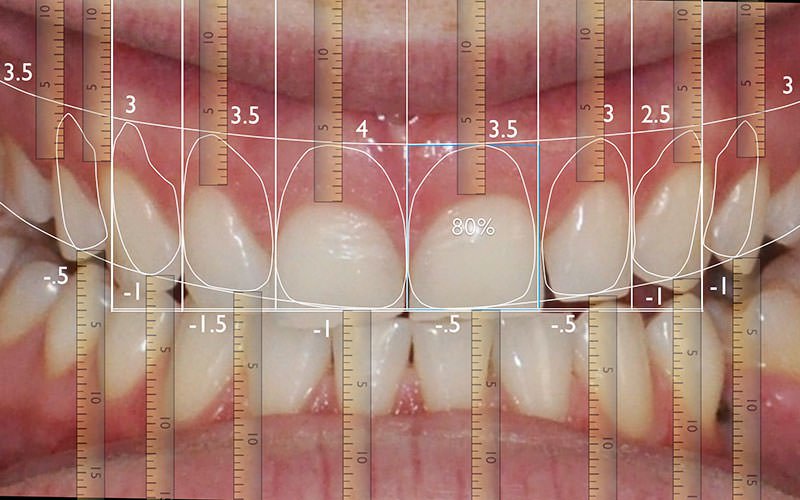

Consiste em um ensaio fotográfico prévio onde são realizados imagens digitais em alta resolução do sorriso, dentes e face do paciente. Essas imagens são inseridas em um software e analisadas minunciosamente.

Após analise fotográfica, um projeto de um novo sorriso é desenhado, individualmente, em computador e analisado digitalmente, podendo ser compartilhado e visualizado pelo paciente e dentista antes de ser posto em prática.

O grande objetivo do DSD é criar um design de sorriso que esteja de acordo com as necessidades funcionais, estéticas e até emocionais do paciente, como ter um sorriso mais delicado, mais extrovertido ou mais intenso. Palavras que se materializam na transportação virtual do sorriso, antecipando o resultado esperado.